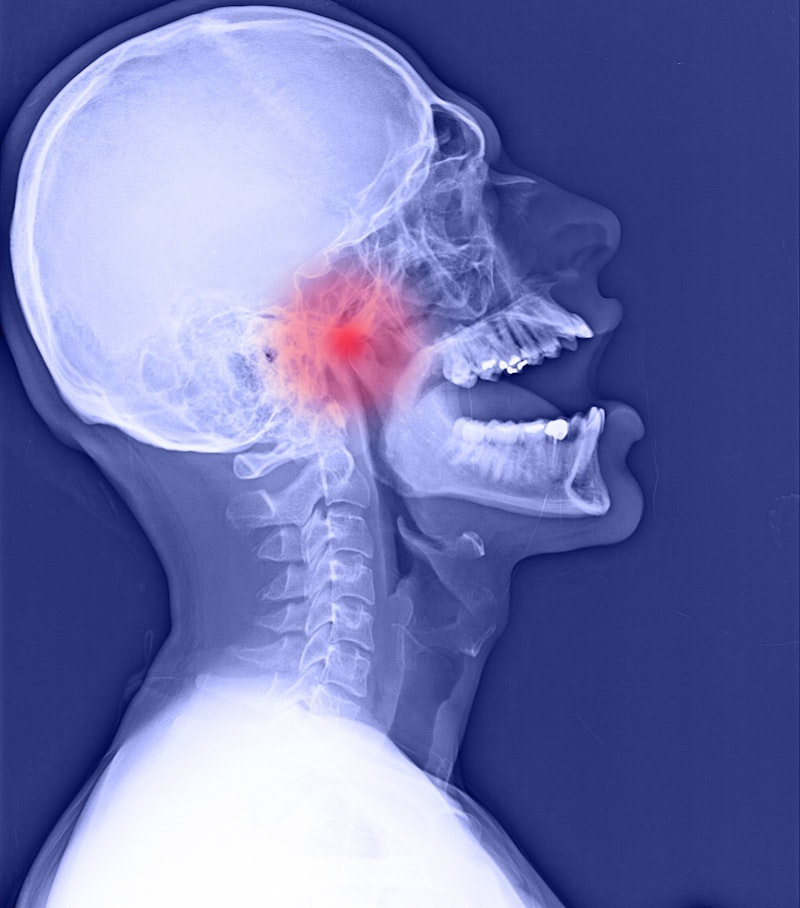

Your temporomandibular joints (TMJ) are located just in front of each ear. These complicated joints are responsible for many jaw movements, allowing you to talk, chew, yawn, and so forth. A TMJ disorder (TMD) refers to improper function of the jaw joint.

TMJ disorders can affect the soft cartilage disc of your TMJ, the bones of the joint itself, the muscles that surround the jaw, or the nerves near the jaw and ear.

Our Fairfax dental office will use the latest X-ray and 3D scanning technology to identify the various structural issues that could contribute to poor bite alignment, teeth grinding, or suboptimal jaw function.